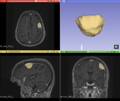

Automatic segmentation with ANTs usually could not distinguish the tumor from the rest of the brain.

We tried FSL's FAST with different numbers of classes. None of these methods could identify the entire tumor mass as one type of tissue in this scan.

FAST brain segmentation with 3 classes

FAST brain segmentation with 4 classes

FAST brain segmentation with 5 classes